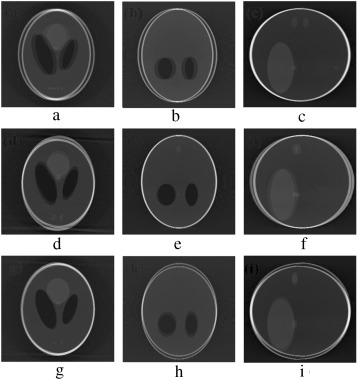

(a–c) Projection at 160°, 180° and 200° source position. (d–f) Axial, coronal ...

Figure 7.

(a–c) Projection at , and source position. (d–f) Axial, coronal and sagittal slices of the translational motion corrupted reconstructed volume.

5. Simulation of the marker-based system

In order to validate the functionality of our proposed Marker-Based Motion Detection (MBMD) and artifacts mitigation technique (MB_FDK algorithm), we need to first simulate motion artifacts using our modified 3D Shepp–Logan phantom. For simulating motion artifacts, we need to perturb the 3D Shepp–Logan phantom during data acquisition time. Using the modified X-ray projection equation  [17] , which incorporated three translational and three rotational (roll, pitch, yaw ) parameters of motion, we simulated several abrupt and gradual variations of motion on the 3D Shepp–Logan phantom. The cone-beam parameters listed in Table 2 are used for our simulation. For abrupt variation of motion, we perturbed the 3D Shepp–Logan phantom with three different types of motion (translational, rotational, and rotational & translational combined) in three different test cases. Some of the images of motion corrupted projections and the axial, coronal and sagittal slices of the reconstructed volume of the above cases are plotted in Figure 7 , Figure 8  and Figure 9 . For gradual variation of motion, we varied each parameter of motion separately in six different test cases. For gradual translational motion corruption cases, we gave ±6 mm of perturbation with a step size of ±1 mm. For gradual rotational motion corruption cases, we gave perturbation of ±5° with a step size of ±1°. The axial, coronal and sagittal slices of the gradual motion corrupted cases (+ perturbation only) are plotted in Figure 10a  and Figure 10b . Figure 10a  and Figure 10b show the motion artifacts created in the reconstructed image due to the gradual perturbation given to the 3D Shepp–Logan phantom during data acquisition time. In Figure 10a , the 1st row shows the artifacts occurred due to the perturbation of +6 mm with a step size of +1 mm along the -axis given. The 2nd and 3rd rows show the artifacts created due to the similar perturbation given to the phantom along the and axes, respectively. In Figure 10b , the 1st row shows the motion artifacts (artifacts dominant in the axial slice) occurred due to the rotational perturbation of 5° (clock-wise) with a step size of 1° given about the -axis (yaw). The 2nd row shows the motion artifacts (artifacts dominant in the sagittal slice) occurred due to the same rotational perturbation about the -axis (pitch). The 3rd row shows the artifacts (artifacts dominant in the coronal slice) occurred due to the rotational variation of similar motion about the -axis (roll). From Figure 7 , Figure 8 , Figure 9 , Figure 10a  and Figure 10b , it can be observed that head motion during data acquisition time resulted in doubling, ghosting, blurring and loss of resolution artifacts in the reconstructed images.